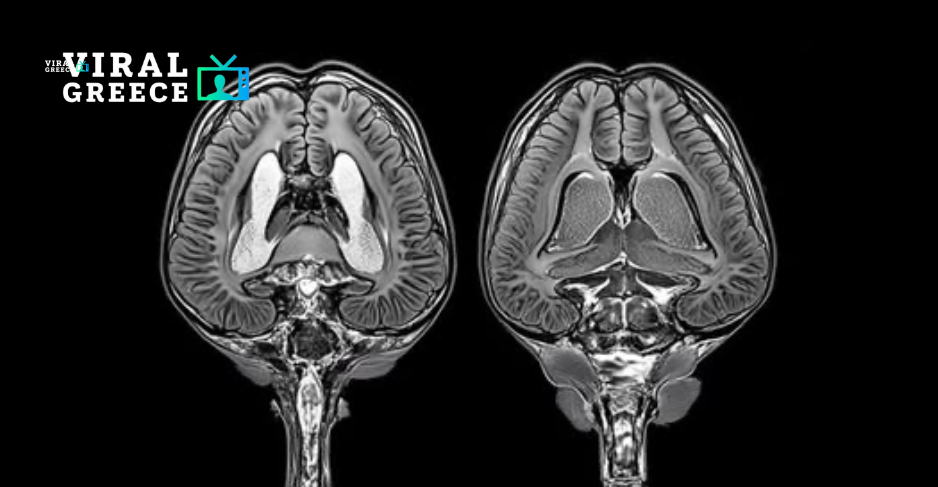

Μια νέα έρευνα αποκαλύπτει μια ανησυχητική σύνδεση ανάμεσα στη χρόνια στέρηση ύπνου και στη μακροχρόνια βλάβη του εγκεφάλου.

Επιστήμονες που μελέτησαν ποντίκια με ελλιπή ύπνο διαπίστωσαν ότι η παρατεταμένη αϋπνία οδηγεί τα ανοσοκύτταρα του εγκεφάλου—τα αστροκύτταρα και τη μικρογλία—σε υπερδραστηριότητα.

Τα αστροκύτταρα, τα οποία συνήθως απομακρύνουν τις περιττές συνάψεις, άρχισαν να καταστρέφουν περισσότερες εγκεφαλικές συνδέσεις και κυτταρικά υπολείμματα. Παράλληλα, η μικρογλία, που είναι υπεύθυνη για την απομάκρυνση κατεστραμμένων κυττάρων, εμφάνισε αυξημένη δραστηριότητα.

Αν και αυτές οι διεργασίες μπορεί αρχικά να έχουν προστατευτικό ρόλο, η υπερδιέγερση των συγκεκριμένων κυττάρων έχει συνδεθεί με νευροεκφυλιστικές παθήσεις, όπως η νόσος Αλτσχάιμερ.

Τα ευρήματα αυτά ρίχνουν φως στο γιατί η χρόνια στέρηση ύπνου συνδέεται όλο και περισσότερο με αυξημένο κίνδυνο άνοιας και γνωστικής εξασθένησης. Ο ύπνος είναι ζωτικής σημασίας για τη συντήρηση του εγκεφάλου – απομακρύνει τοξικά απόβλητα, ενισχύει τη μνήμη και σταθεροποιεί σημαντικές νευρωνικές συνδέσεις.